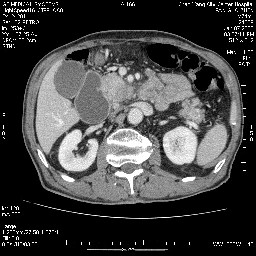

女,74岁,呕吐10余日

考虑来源于十二指肠水平段的恶性占位,侵及周围组织,特别是胰腺,可见区域淋巴结肿大,左侧下腔静脉畸形。

十二指肠水平段腔内占位伴梗阻,中等度较为均匀的强化,洗脱慢,区域淋巴结显示增多,符合腺癌表现。下腔静脉变异。

病变主要位于钩突(癌)。如是壶腹部,肝内外胆管扩张明显。

十二指肠降段扩张,水平段狭窄成鼠尾状,肠壁明显增厚,胰腺勾突增大成不均匀强化,其内可见低密度区,胆囊增大,1十二指肠水平段腺癌侵犯胰腺勾突可能大,2胰腺癌侵犯十二指肠(只有胆囊增大没有肝内外胆管扩张不好解释)代除外.

十二指肠降段扩张,水平段狭窄成鼠尾状,肠壁明显增厚,胰腺勾突增大成不均匀强化,其内可见低密度区,胆囊增大,1十二指肠水平段腺癌侵犯胰腺勾突可能大,2胰腺癌侵犯十二指肠 。

今日手术结果:胰腺钩突癌侵犯十二直肠,腹腔淋巴结转移.